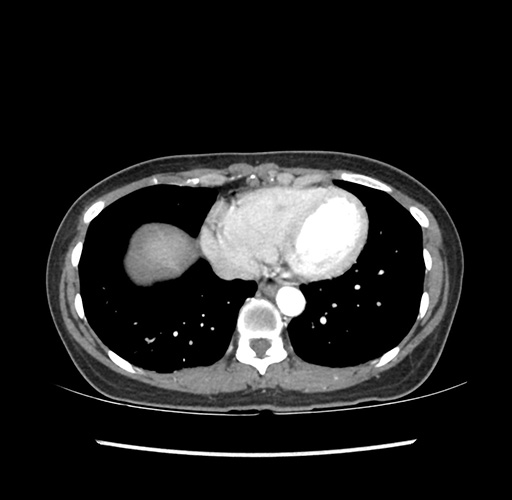

Imaging Analysis

Look through the patient's CT scan to identify any areas of concern for the necessary procedure.

Based on your CT findings, which issue(s) would give reason for "planned slowing down moment(s)" in this case?

Considering a standard left lateral sectionectomy procedure, what step(s) of the operation would you do differently in this case ?